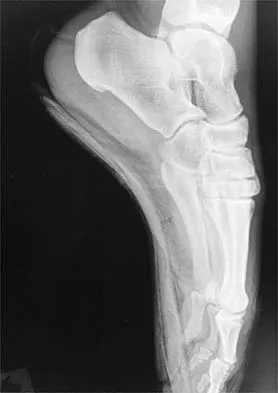

Figures 4a through 4c show the radiographs of a 43-year-old woman who sustained a twisting injury to her right ankle. She has ankle pain and tenderness medially and laterally. To help determine the optimal treatment, an external rotation stress radiograph of the ankle is obtained. This test is designed to evaluate the integrity of what structure?

Explanation

In the presence of a supination external rotation-type fracture of the distal fibula (Weber type B), stability of the ankle is best assessed by performing an external rotation stress AP view of the ankle. This test is used to assess the integrity of the deltoid ligament. The presence of a deltoid ligament rupture results in instability and generally is best managed surgically. The gravity stress test can also be used. Egol KA, Amirtharajah M, Tejwani NC, et al: Ankle stress test for predicting the need for surgical fixation of isolated fibular fractures. J Bone Joint Surg Am 2004;86:2393-2398. McConnell T, Creevy W, Tornetta P III: Stress examination of supination external rotation-type fibular fractures. J Bone Joint Surg Am 2004;86:2171-2178.